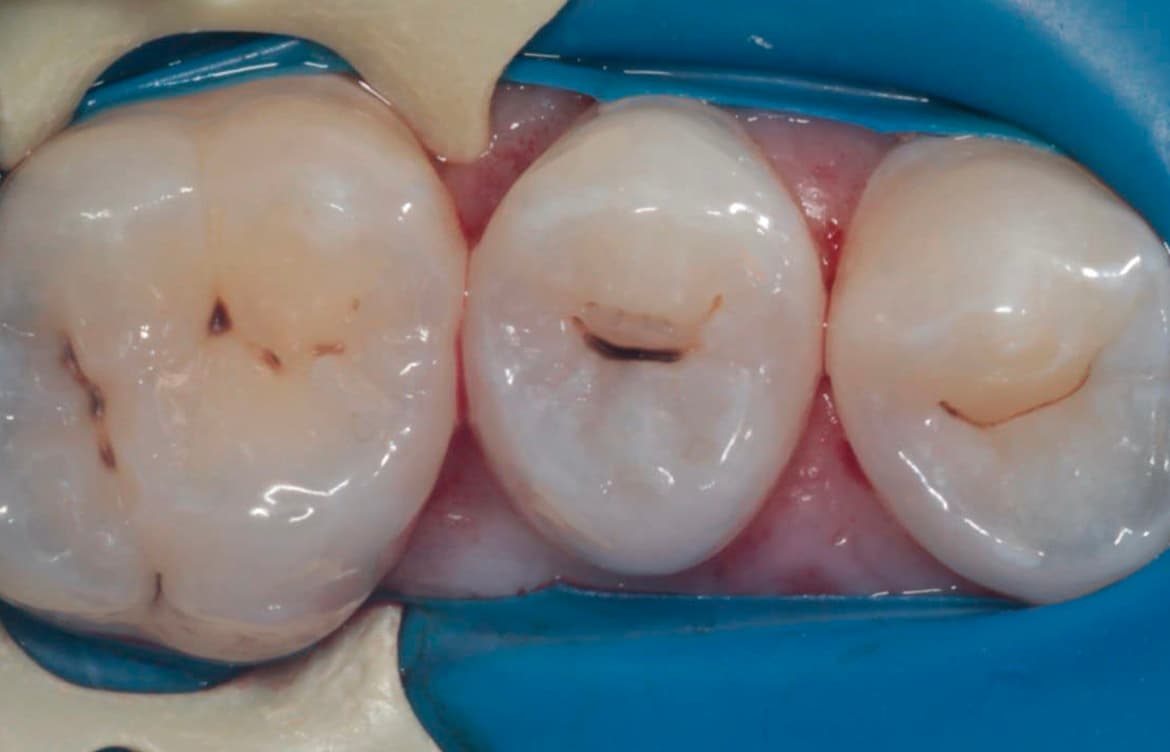

Наши работы